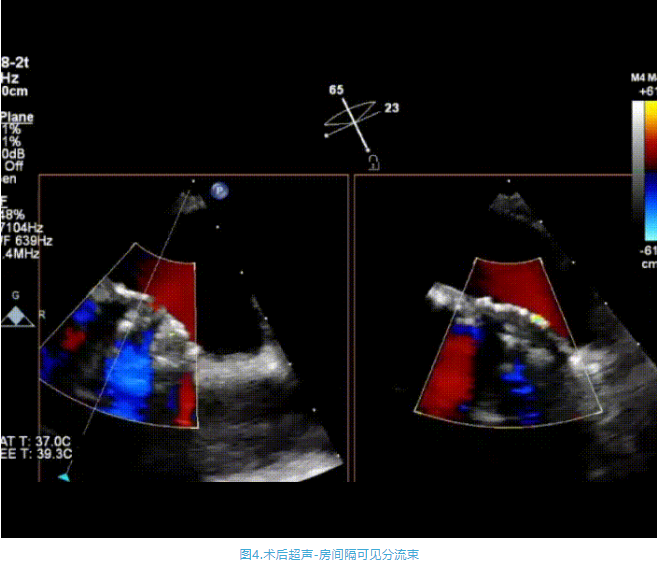

術中首先在局麻下穿刺股動脈、股靜脈,完成心導管檢查評估后轉為全麻,在食道超聲引導下穿刺房間隔,穿刺成功后將加硬導絲送入左上肺靜脈建立軌道,根據患者病情行球囊預擴張后植入6mm孔徑房間隔造孔支架,經透視及食道超聲評估支架左右盤展開良好,夾持于房間隔兩側,固定穩定、位置良好,食道彩超顯示房水平右向左為主分流,分流孔直徑符合預期大小,心導管檢查評估達到預期效果,釋放造孔支架。術后12h患者下床活動,恢復順利,擬于近日完善術后評估后出院。

心房分流術是通過器械制造穩定可控的心房間分流,適應證包括藥物治療效果不佳的左心衰或肺動脈高壓右心衰。本例患者為肺動脈高壓右心衰,術中成功放置MicroFlux®造孔支架在房間隔理想位置上,創造穩定可控的心房間分流(此例患者以右向左分流為主),在不顯著增加左心負擔的情況下,有效降低患者右心房壓力、緩解體循環淤血,增加左心輸出量,改善患者癥狀、活動耐力和生存質量。同時,國內外也已經開展多項房間隔造孔支架在射血分數保留、射血分數中間值和射血分數降低的左心衰患者中的臨床研究,結果顯示對于經過充分的規范化藥物治療后仍控制不佳的患者,心房分流術可改善患者的癥狀及生存質量?! ?/p>